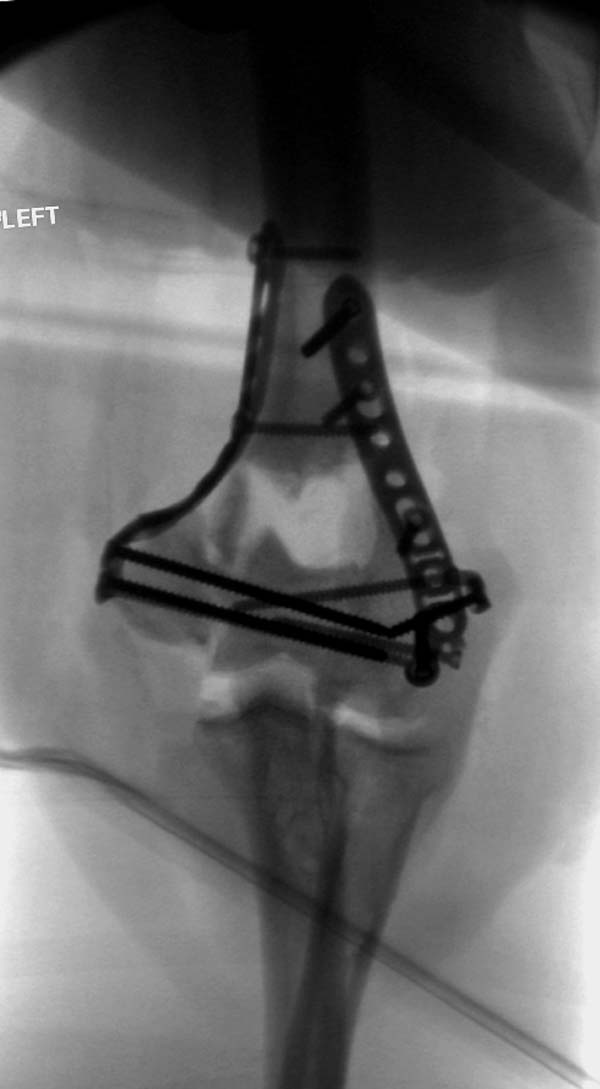

Примеры: первому более 15 лет фиксирован шурупом и tension band

technique, а второй перелом открытый больной 80 лет, после наружного

фиксатора в первом этапе и окончательная фиксация вторично. Третьий раз

внесуставная остеотомия...